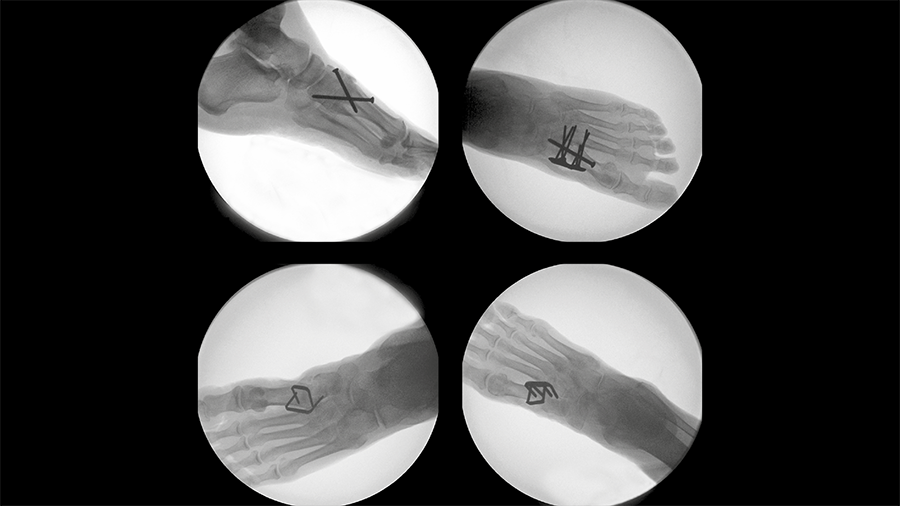

DPS Hammertoe CCI

First extramedullary continuous compression implant to treat hammertoe deformities.

Tarsometatarsal joint fusion

Nitinol stables might demonstrate comparable performance to established techniques for fusion of the first TMT joint.